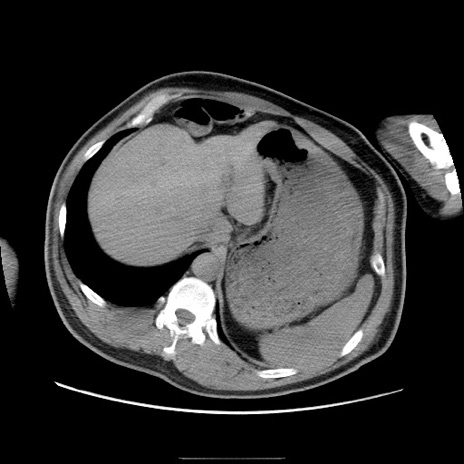

冠状断像

【症例】50歳代男性

【主訴】腹痛

【現病歴】AVMからの被殻出血のため回復期リハ病棟入院中。 本日午後3時頃急に下腹部痛が出現した。

【既往歴】AVM、被殻出血、虫垂炎、高血圧

【身体所見】意識晴明、左半身不全麻痺、会話の理解は良好、36.5°C、腹部:膨隆、全体に板状硬、下腹部正中に圧痛点あり、反跳痛-、筋性防御不明、右下腹部にope scar

【データ】WBC 9400、CRP 0.06